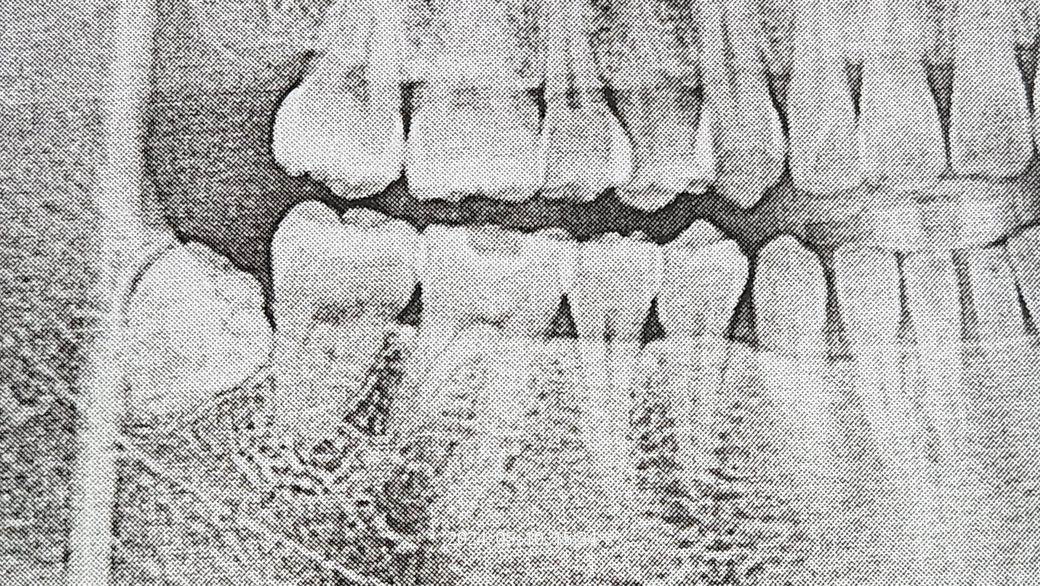

기형치 매복사랑니 발치해야할까요?

오른쪽에 매복사랑니가 있는데요

지금은 크게 아프거나하는건 없는데 기형적으로 생겨서

옆 어금니에 문제가 생길거같은데..발치해야되나요??

현재 앞의 어금니 뿌리맞닿아 있어 영향을 주고 있기에 사랑니를 우선적으로 발치하는 것이 필요로 됩니다. 매복 사랑니 발치는 난이도가 있기에 경험이 풍부한 구강외과 전문의가 있는 곳에서 발치를 권합니다.

안녕하세요 치과의사 김철진입니다. 올려주신 사진에는 사랑니가 제대로 보이진 않습니다. 얼핏보면 매복치인신거 같은데 특별한 이유가 없다면 발치를 하지 않으셔도 큰 문제가 잇진 않을것같습니다.

모양이 기형적으로 생겼다고해서 옆 어금니에 영향을 끼치는 것은 아니며 어금니가 옆으로 누워 옆 어금니와 겹쳐있을때, 밀고 있을 때 옆 어금니에 충치를 유발하거나 치아뿌리를 흡수시킬 수 있습니다. 보통 부분매복 상태의 사랑니는 문제를 일으키기 전 예방적 발치를 권장합니다.